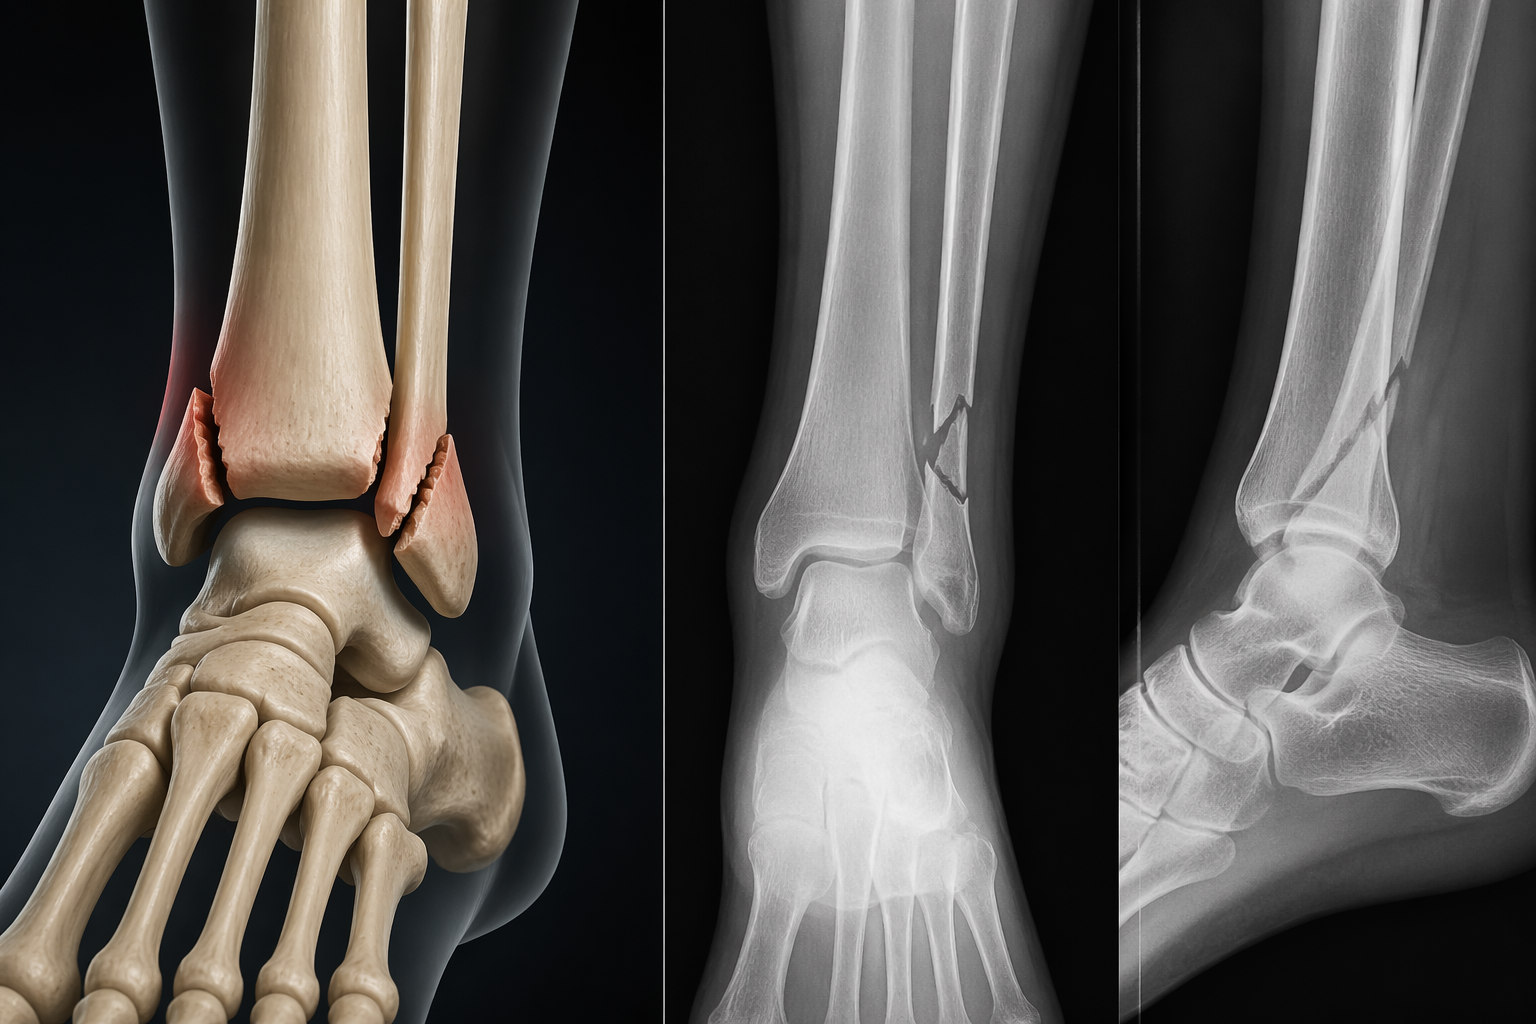

Ayak bileği kırığı, ayak ile bacak arasındaki bağlantıyı sağlayan kemiklerin (tibia, fibula ve talus) herhangi birinde meydana gelen çatlak veya tam kırılma durumudur. Günlük yaşamda oldukça sık karşılaşılan bu yaralanma, spor aktiviteleri, düşmeler veya trafik kazaları gibi çeşitli nedenlerle ortaya çıkabilir. Ayak bileği, vücut ağırlığını taşıyan ve hareket kabiliyetini sağlayan kritik bir eklem olduğu için bu bölgede meydana gelen kırıklar, kişinin yaşam kalitesini ciddi şekilde etkileyebilir.

Ayak bileği kırıkları, basit bir çatlak şeklinde olabileceği gibi cerrahi müdahale gerektiren ciddi hasarlara da yol açabilir. Bu nedenle erken tanı ve doğru tedavi büyük önem taşır. Özellikle uzman görüşü almak, iyileşme sürecini hızlandırır ve kalıcı hasar riskini azaltır. Bu noktada ortopedi uzmanlarının değerlendirmesi hayati rol oynar.

Tanı Yöntemleri

Ayak bileği kırığının doğru şekilde teşhis edilmesi tedavi sürecinin en önemli adımıdır. Tanı yöntemleri şunlardır:

Fizik Muayene: Doktor, ayağın durumunu değerlendirir, hassasiyet noktalarını inceler ve hareket kabiliyetini test eder.

Röntgen: En yaygın kullanılan görüntüleme yöntemidir. Kırığın yeri ve tipi hakkında bilgi verir.

MR ve BT: Daha detaylı inceleme gerektiğinde kullanılır. Özellikle bağ dokusu ve yumuşak doku hasarlarını belirlemede etkilidir.